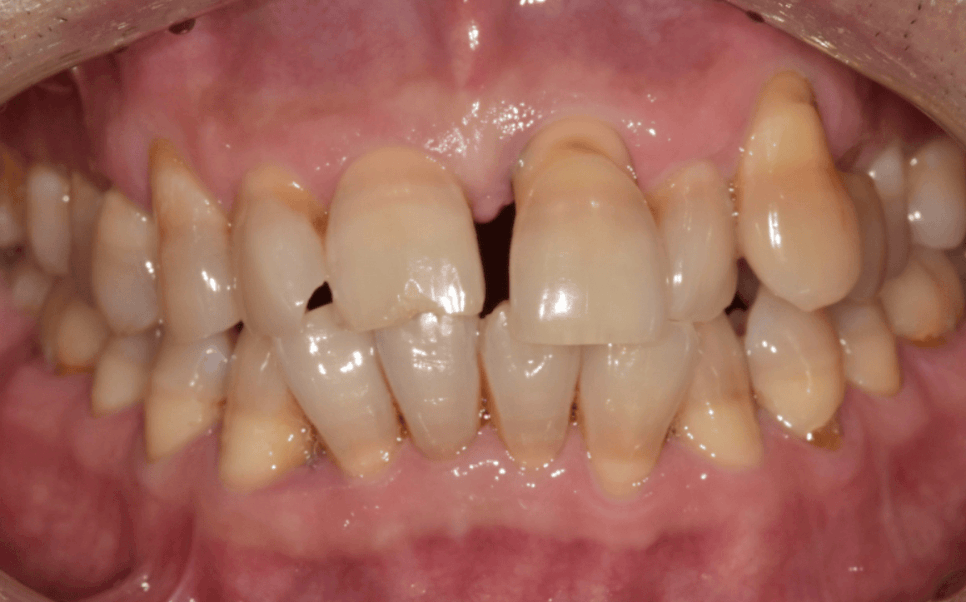

정확한 상태 확인을 위해 엑스레이 촬영과 검사를 진행한 결과,

치석으로 인해 잇몸병이 진행되면서

잇몸뼈가 일부 녹아 있는 상태였습니다.

230413 / 230417

잇몸뼈가 줄어들면

치아를 받쳐주던 힘이 약해집니다.

그 결과 치아가 제자리에서 점점 내려오고,

치아가 길어 보이게 됩니다.

이 정도 상황에서는 발치로 이어지는 경우도

적지 않습니다.

하지만 이 환자분은 앞니를

지지하는 뼈가 완전히 무너진 상태는 아니었고,

치아 흔들림도 심하지 않아

자연치아를 살리는 방향으로 계획을 세울 수 있었습니다.

또한 과거 대장암으로 오랜 기간 치료를 받으신 병력이 있어 가능하면

“치아를 최대한 살리고 싶어요"라고 말씀하셨습니다.

이에 저희도 같은 목표를 가지고

무리한 발치 대신,

잇몸치료와 보존 치료를 우선으로 진행했습니다.

뼈를 녹인 치석들을 제거하고 염증 조직들을 꼼꼼하게 제거한 뒤

잇몸을 다시 건강하게 회복시키는 것이 목표.

또한 치아 뿌리가 드러나 마모된 상태였고

시린 증상이 있어 신경치료를 함께 진행했습니다.